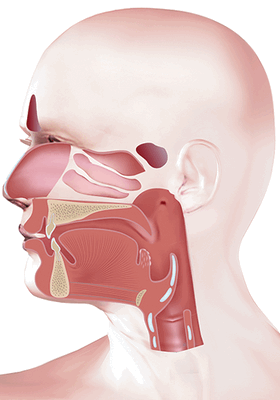

Анатомическое строение

Ротоглотка - это продолжение носоглотки, средний отдел гортани. Она начинается от твердого неба и заканчивается у входа в гортань. Орган соединяется с полостью рта зевом, а отделяется небными дужками, мягким небом и спинкой языка. В этом отделе перекрещиваются пищеварительные и дыхательные пути. В состав ротоглотки входит:

- задняя треть языка (его корень);

- миндалины;

- задние и боковые стенки глотки. Задняя стенка находится на уровне третьего шейного позвонка. Боковые стенки соединяются с евстахиевыми трубами ушей.